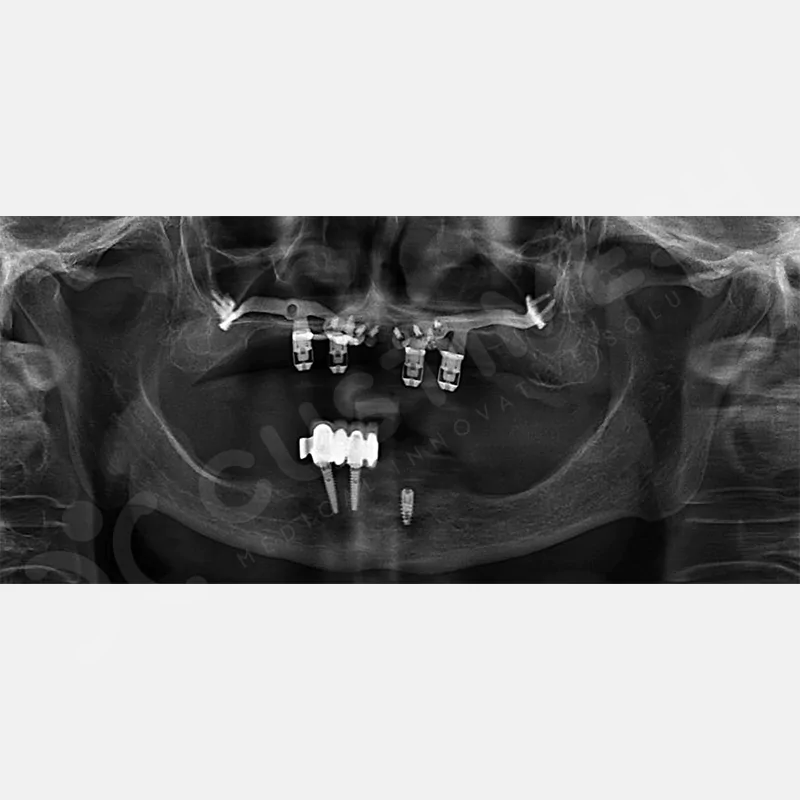

VAKA 1

VAKA 2

VAKA 3

VAKA 4